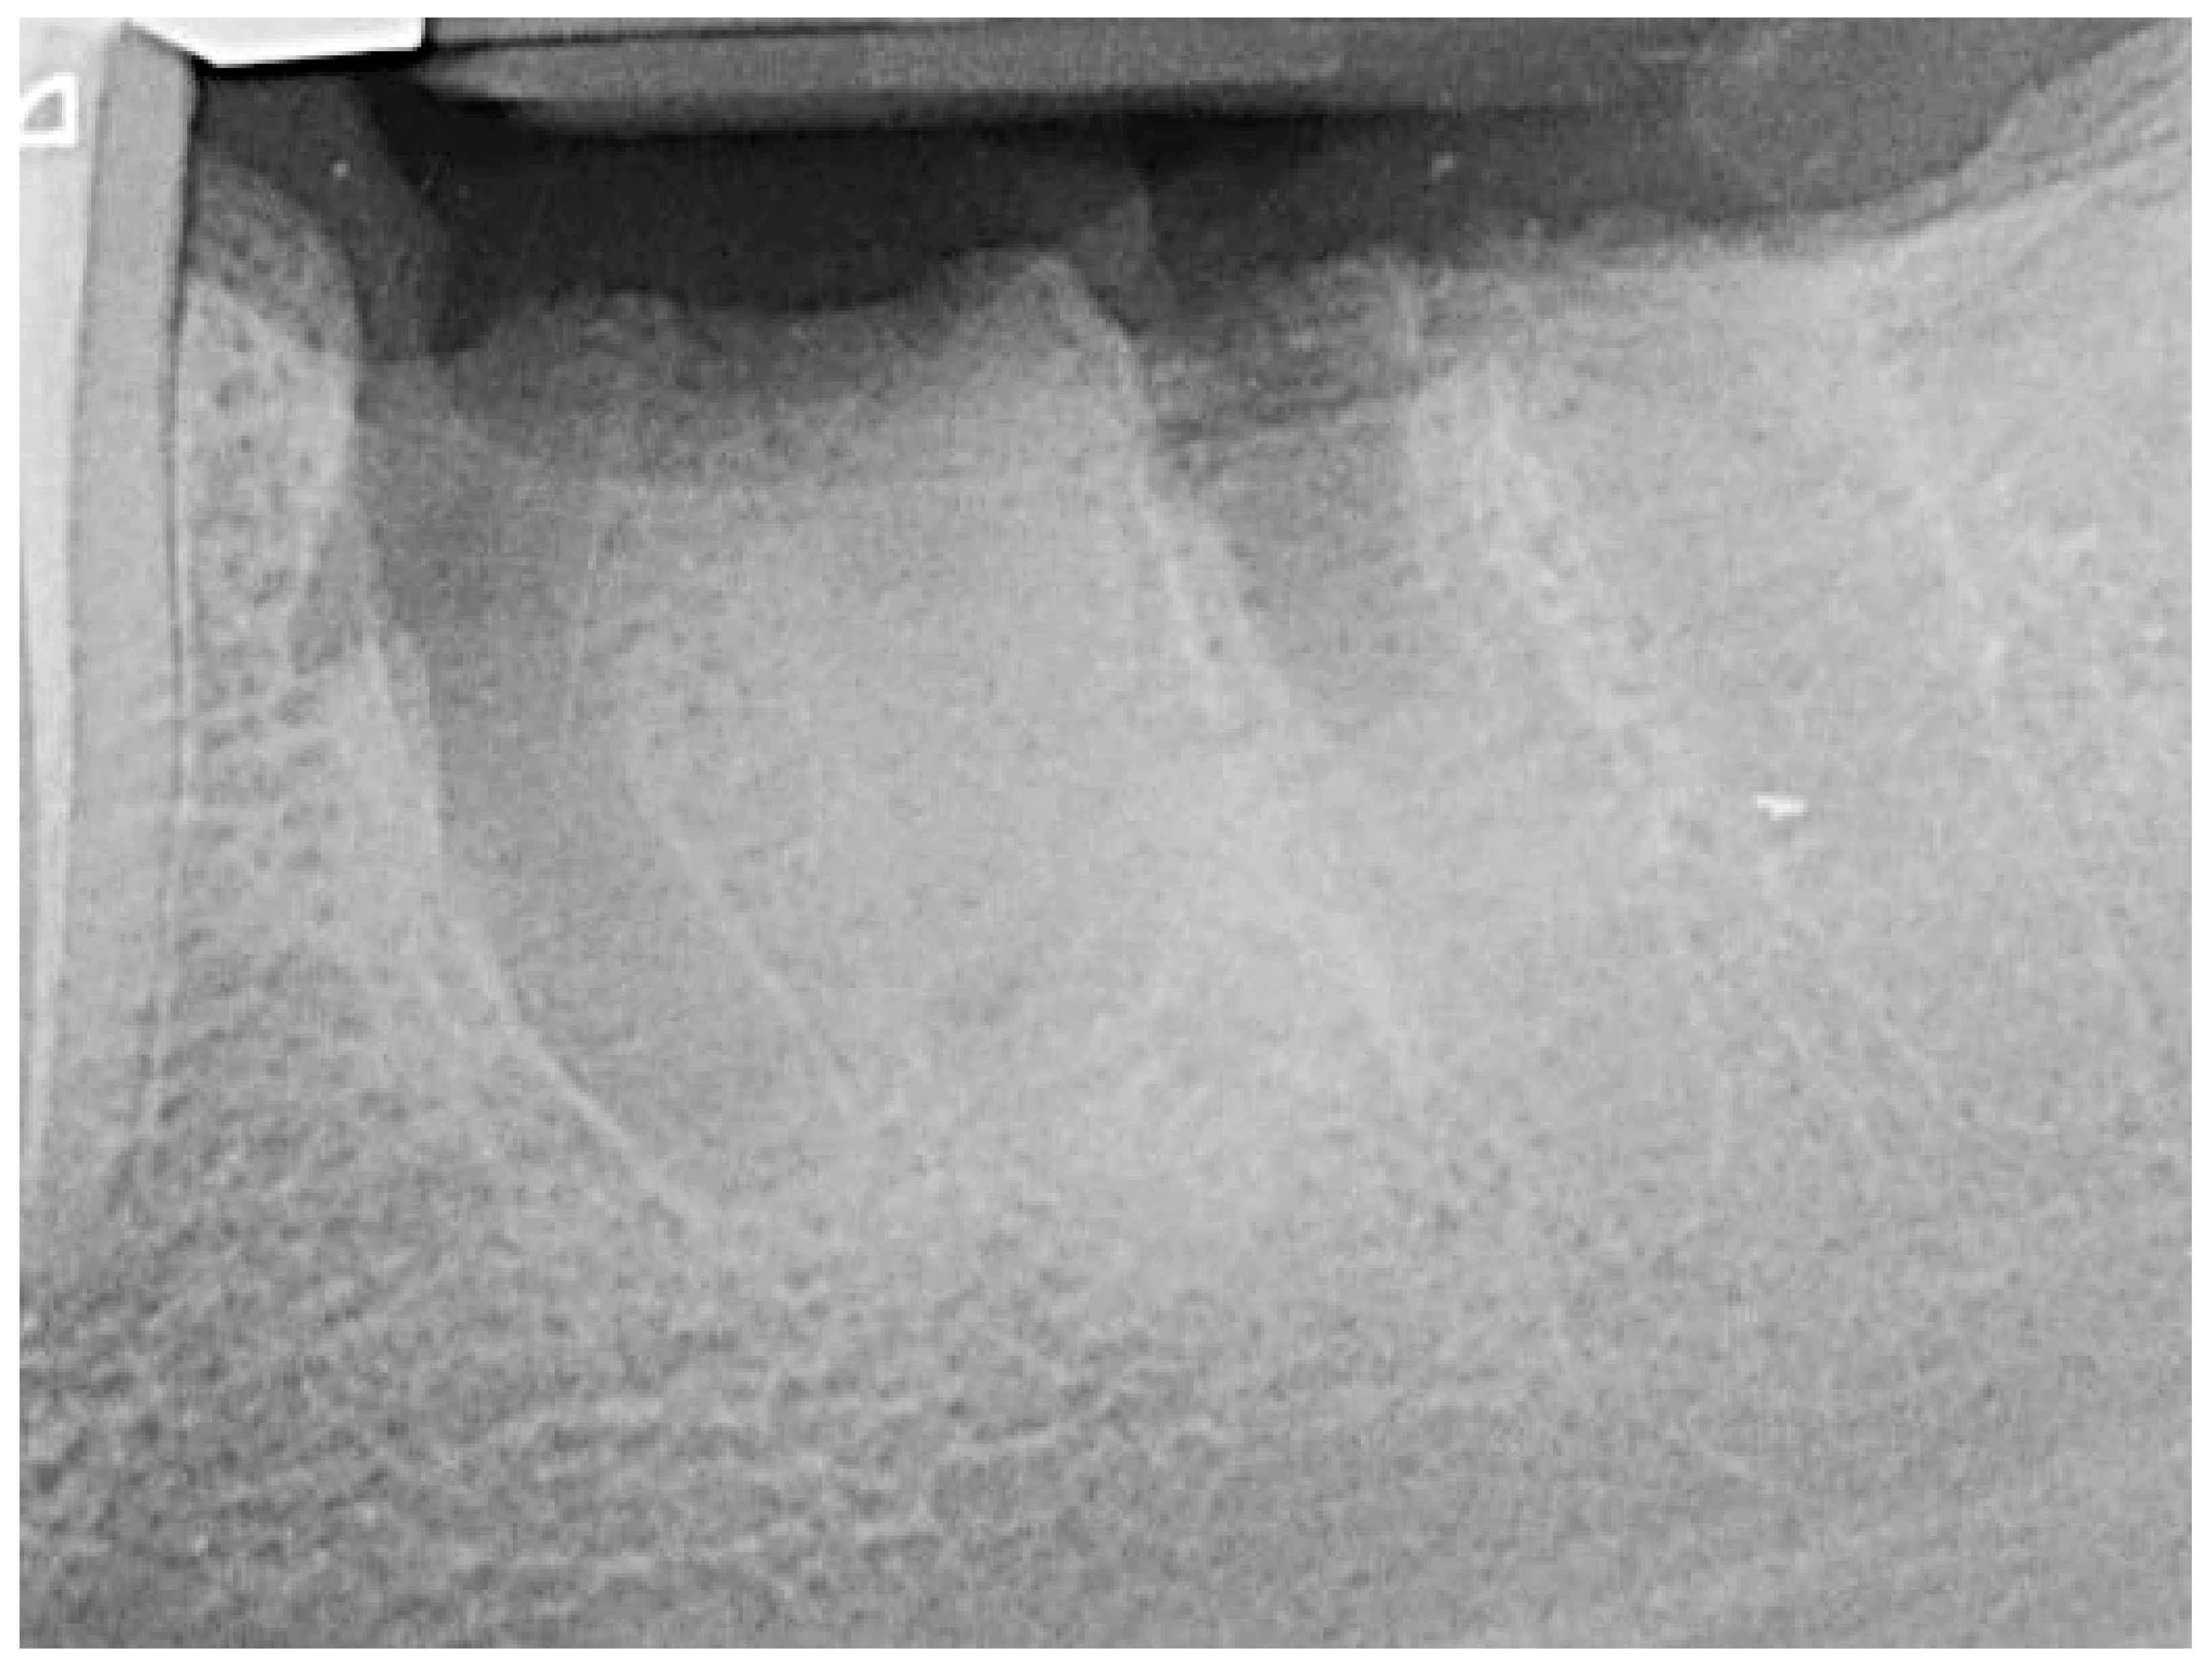

Figure 5.

Socket 36 after alveolar ridge preservation.